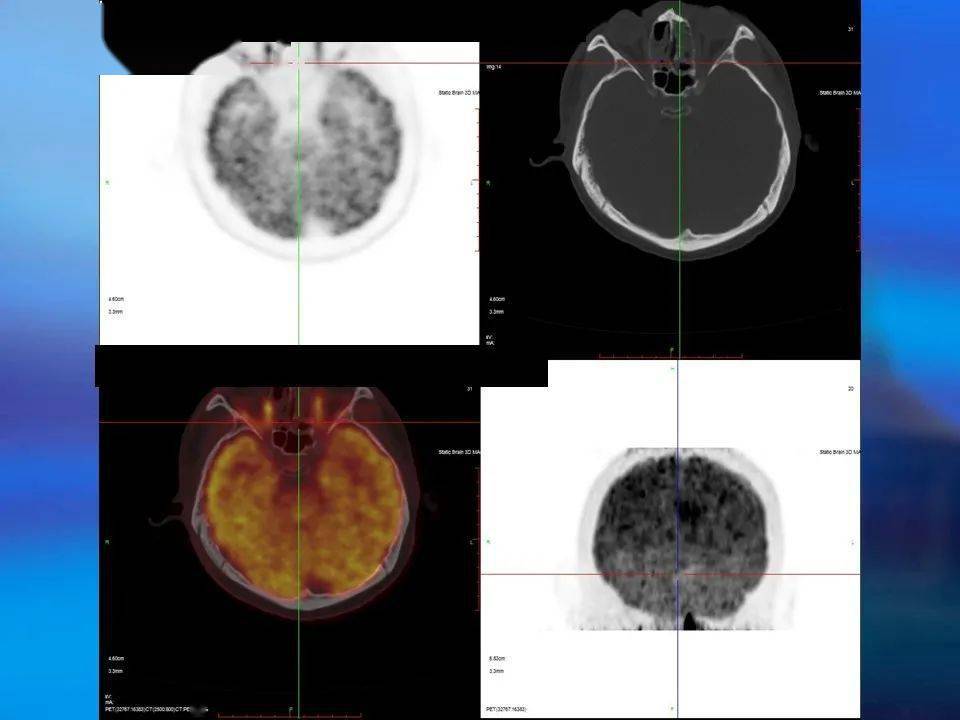

根据脑电图,头部mr,脑磁图及pet—ct检查提示,右侧额癫痫样放电,右额